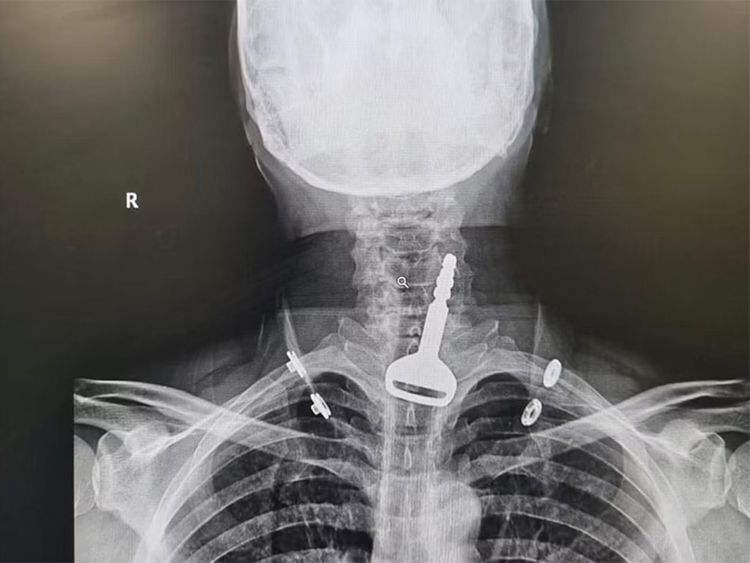

وقتی این مرد پس از حادثه به بخش اورژانس بیمارستان برده شد، پزشکان با انجام تصویربرداری اشعه ایکس توانستند محل قرار گرفتن سوئیچ در مجرای تنفسی این مرد را بیابند. از آنجاییکه این مرد مشکل قلبی هم داشت، شرایط هم پیچیدهتر شده بود. اما خوشبختانه عمل لاپاروسکوپی موفقیتآمیز بود و این مرد عربستانی از این حادثه جان سالم بهدر برد.